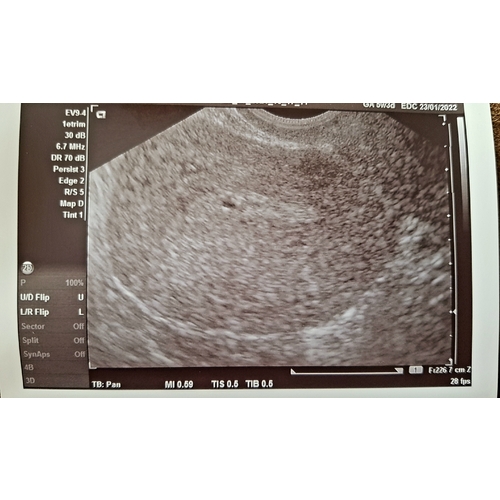

Dit was 5+5 kweet niet of je hier veel mee bent... Weet wel, als ze tellen vanaf je laatste menstruatie en je hebt een lange cyclus ben je 1week minder ver dan gedacht. En als je innesteling eerder tegen dag 12 ipv dag 7 was, scheelt het ook bijna een week. Ik ben zo van 7+2 naar 5+5 gezet